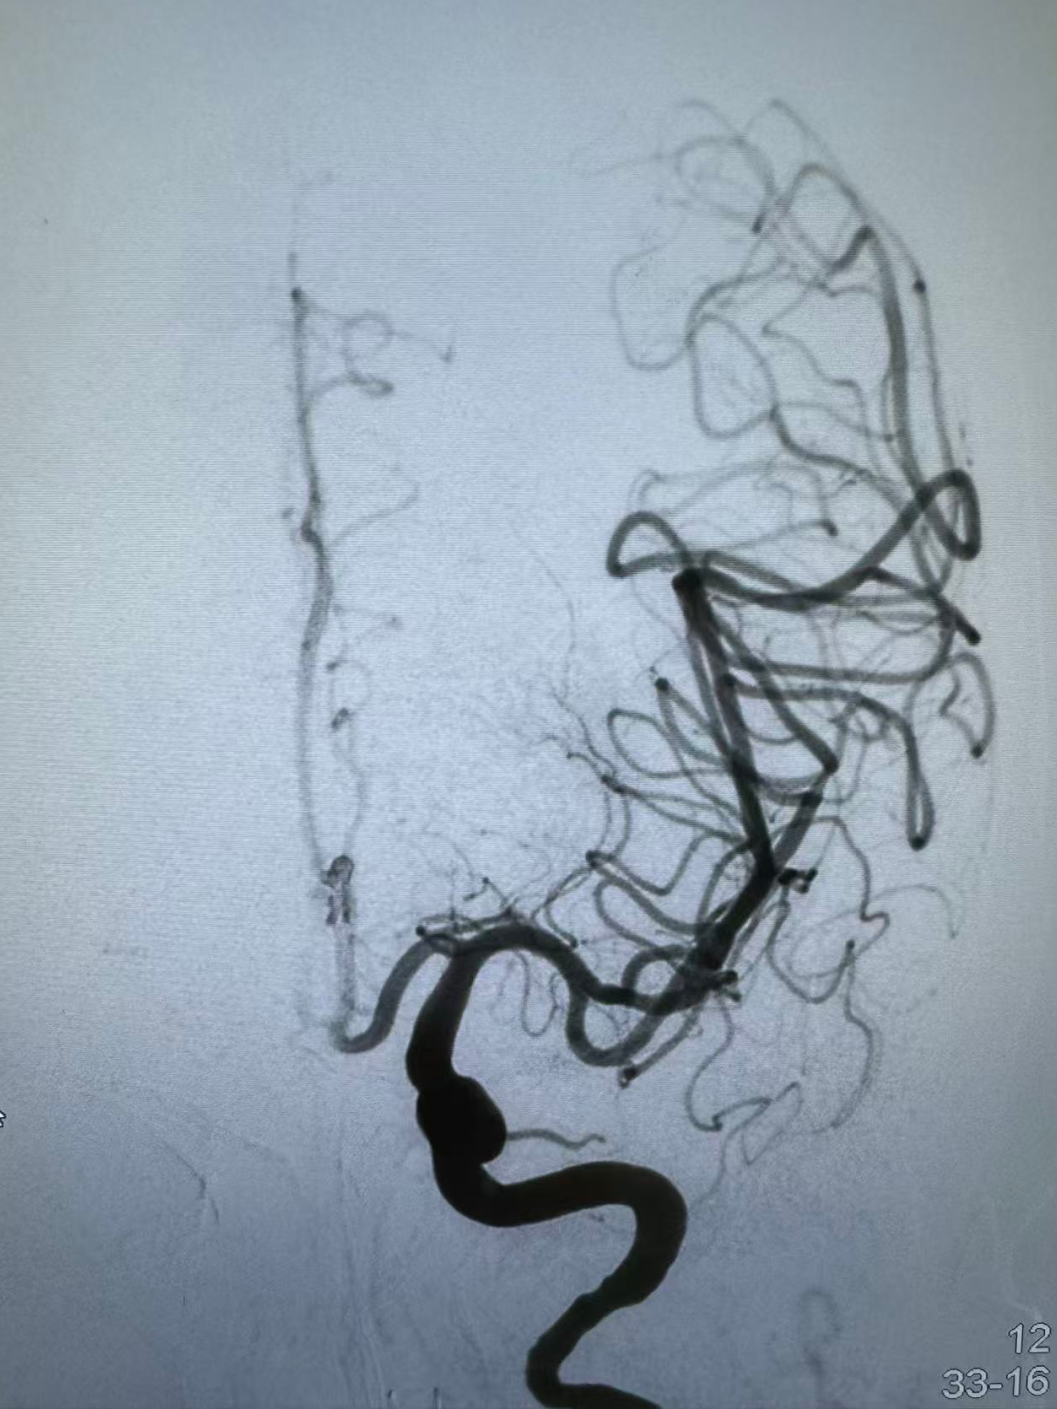

弓上造影:II型弓,大脑中动脉栓塞。

确认血栓完全取出后,球囊泄压,术后即刻造影显示大脑中动脉闭塞再通, mTICI评分3级。

无明显造影剂渗漏及脑梗死表现。